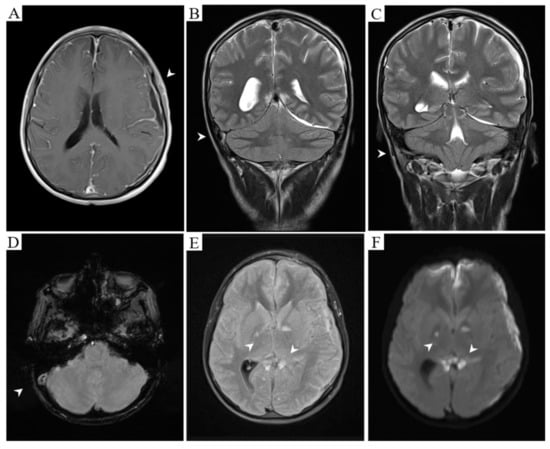

On the initial evaluation by Neurology, the patient was under sedative medications, intubated, with right oculomotor palsy (mydriasis and eye abduction in the primary position of gaze) and neck stiffness. A magnetic resonance imaging (MRI) was required and showed the bilateral globus pallidus, internal capsule, corpus callosum, and left uncal ischemic regions. There was empyema in the left fronto-temporo-parietal and right frontal regions with lepto- and pachymeningeal enhancement. Furthermore, angio-MRI was highly suggestive of right transverse and sigmoid venous sinuses thrombosis (Figure 1).

Figure 1.

Meningeal enhancement and left fronto-temporo-parietal empyema. Empty delta sign is also observed (A, T1 post-gadolinium). Right transverse (B, T2) and sigmoid (C, T2) sinuses occlusion due to an acute thrombus (D, Gradient echo). Established ischemia affecting bilateral globus pallidus and corpus callosum splenium (E, T2 FLAIR) with diffusion restriction (F, DWI).